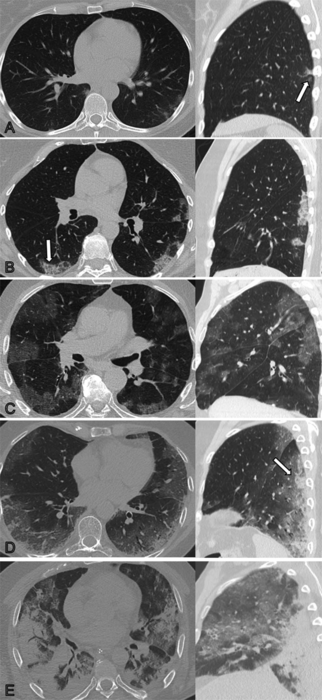

OAK BROOK, Ill. (March 29, 2022) – Some people recovering from COVID-19 pneumonia have CT evidence of damage to their lungs that persists a full year after the onset of symptoms, according to a new study published in the journal Radiology .

As part of an Austria-based observational study on the development of lung disease in patients with SARS-CoV-2 infection, researchers looked at patterns and rates of improvement of chest CT abnormalities in patients one year after COVID-19 pneumonia. CT has been an important imaging tool in the workup of patients suspected of having COVID-19.

The researchers assessed lung abnormalities on chest CT in 91 participants, mean age 59 years, at several points over one year after the onset of COVID-19 symptoms.

At one year, CT abnormalities were present in 49, or 54%, of the 91 participants. Of these 49 participants, two (4%) had received outpatient treatment only, while 25 (51%) were treated on a general hospital ward and 22 (45%) had received intensive care unit (ICU) treatment.

“The observed chest CT abnormalities from our study are indicative of damaged lung tissue,” said study co-author Anna Luger, M.D., from the Department of Radiology at Innsbruck Medical University in Innsbruck, Austria. “However, it is currently unclear if they represent persistent scarring, and whether they regress over time or lead to pulmonary fibrosis.”

While CT abnormalities decreased in initial follow-ups, 63% of participants with abnormalities did not show any further improvement after six months. Age over 60 years, critical COVID-19 severity and male gender were associated with persistent CT abnormalities at one year.